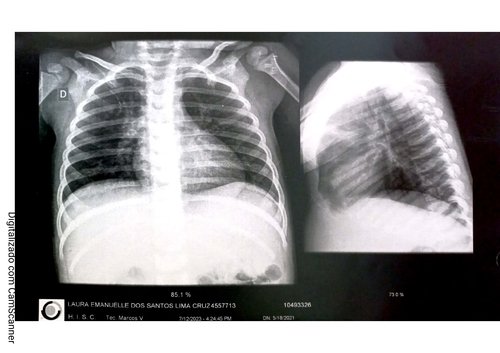

Eu sou a Hellen e criei essa vaquinha para ajudar à Laura Emanuelle, neta de um amigo, Arineu. A Laura tem dois aninhos e sofre com estreitamento do canal respiratório e glândulas aumentadas, causando obstrução nasal. Ela precisa passar por uma cirurgia chamada adenoidectomia, no valor de 12.000 reais, para conseguir respirar normalmente. A mãe deixou o emprego para cuidar da Laura, que tem uma saúde frágil devido à sua condição.

Seguem abaixos exames e comprovantes do estado médico da Laurinha: